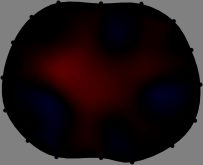

To explain the FER method, we closely examine the correlations among column vectors of the sensitivity matrix , described in Fig. 2. The correlation between and can be expressed as

for [23]. This shows that the column vector is like an EEG (electroencephalography) data induced by dipole sources with directions at locations . Given that two dipole sources at distant locations produce mutually independent data, the correlation between and decreases with the distance between and . Fig. 2 shows a few images of the correlation as a function of for four different positions . The correlation decreases rapidly as the distance increases. In the green regions where the correlation is almost zero, is nearly orthogonal to .

Fig. 2 shows that if and are far from each other, the corresponding columns of the sensitivity matrix are nearly orthogonal. This somewhat orthogonal structure of the sensitivity matrix motivates an algebraic formula that directly computes the local ensemble average of conductivity changes at each point using the inner product between changes in the data and a scaled sensitivity vector at that point: